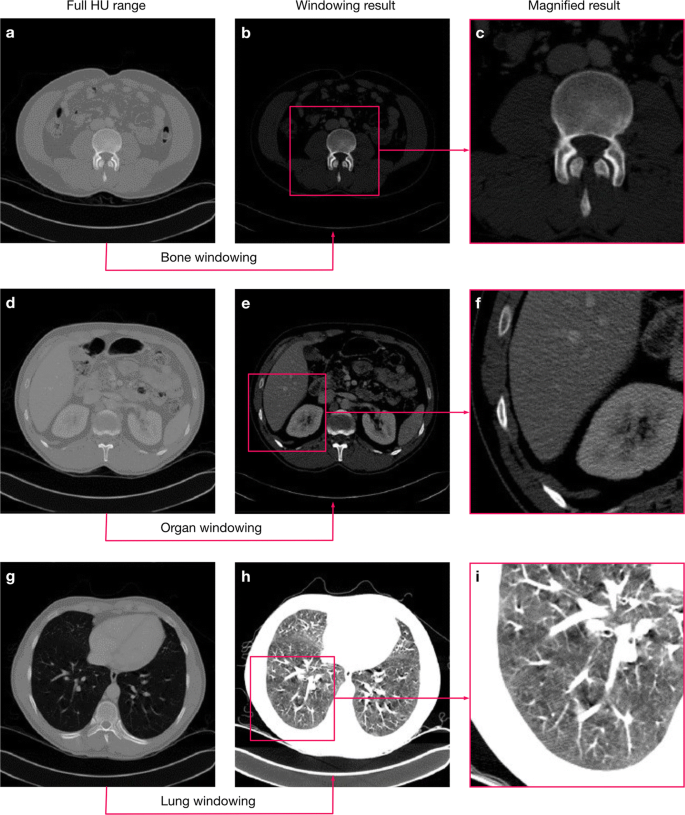

Windowing highlights tissues of interests and reduces the complexity of background structures. Three examples for the use of case-oriented windowing for bones (a–c), organs (d–f), and lungs (g–i). We used the organ oriented windowing in this work, while we show the other two examples for comparison. We derived the intensity windows for CNN processing by slightly extending the standard ranges used by radiologists in practice to allow for uncertainties in the exact ranges.

The tissue-specific information also means, that CT data typically contains a range of values that are not necessarily relevant for a particular diagnostic question8,9. Thus, when radiologists inspect CT volumes for diagnosis, they typically rely on windowing, i.e. they restrict the range of displayed grey values to focus the image information to relevant values. CNN-based image segmentation frameworks rarely include such potentially essential steps from the expert workflow, assuming that the data only has to be normalised and the network will then learn by itself to focus on the relevant image regions.

We adapted the image normalisation from11 to better suit real-world applications. To reduce the complexity and optimise the dynamic range, we apply a windowing to each volume by clipping the voxels grey value range to a (0.6, 0.99) percentile range that corresponds to the window a radiologist would use for decision-making. For other segmentation problems, the percentiles must be adjusted to fit the intensity distribution of the relevant body parts (We show examples in Fig. 1). We then normalise the windowed data using the z-score using the intensity statistics (mean, standard deviation) from a random subset of the data set. Using the intensity statistics from the entire dataset might give slightly better normalisation results, but this approach would not always reflect the typical conditions in a clinical environment. Often, we continuously collected the image data over time and thus, only a subset of the data is available before the training process starts.